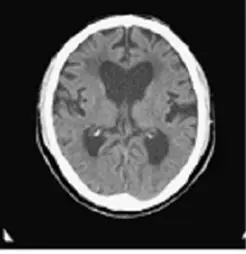

提供的腦部電腦斷層 (CT) 影像顯示:

• 腦室擴大 (Ventriculomegaly):側腦室 (Lateral ventricles) 的額角 (Frontal horns) 明顯擴大。

• 雖然單張影像難以完整評估 DESH (Disproportionately Enlarged Subarachnoid-space Hydrocephalus) 特徵,但可見腦室擴大的程度與腦實質萎縮的程度不成比例(即腦室擴大顯著,但腦溝並未呈現相對應的廣泛萎縮,甚至可能在頭頂部腦溝變窄)。

• 結合病患 65 歲且具有典型三徵 (步態、失智、尿失禁),影像學表現支持 NPH 的診斷。